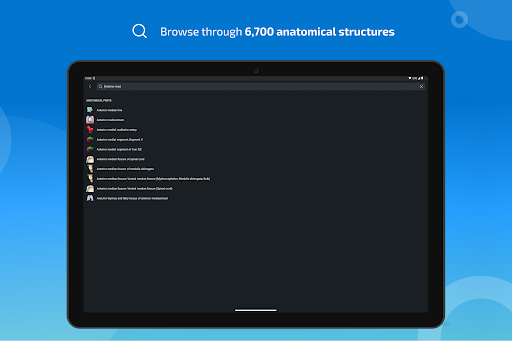

- Localice fácilmente las estructuras anatómicas gracias a la búsqueda de índice

*Encuentre sus partes anatómicas más fácilmente gracias a la nueva función de búsqueda, más intuitiva y poderosa.